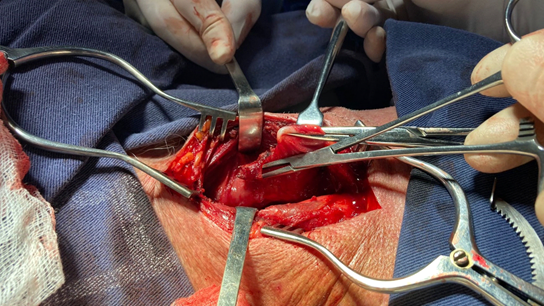

Once the diverticular pouch is identified, it is dissected and released by means of a blunt and gentle maneuver until the neck of the pouch is identified on the posterior pharyngeal esophageal surface. Technically, traction with Allis or dissecting forceps is useful (Figure 6).

Figure 6 Identification and dissection of the diverticular sac. The figure shows the diverticulum tracted from the dissecting forceps. The esophagus is accessed through an alveolar plane medial to the vasculonervous bundle. The cervical spine is used to identify the esophagus which is immediately in front of it. The diverticulum must be dissected with blunt maneuvers up to the esophagus (diverticular neck).

Upon reaching the neck, we can clearly identify the cricopharyngeal muscle in the lower sector, which is loaded with American forceps, taking care not to injure the mucosa and submucosa and sectioning it with ligasure or electric scalpel (Figure 7).

Figure 7 Loading of the cricopharyngeal muscle with American forceps. Once the diverticulum is completely dissected, the cricopharyngeal muscle is loaded, taking care not to injure the mucosa or sub mucosa. It is sectioned with vascular sealants.